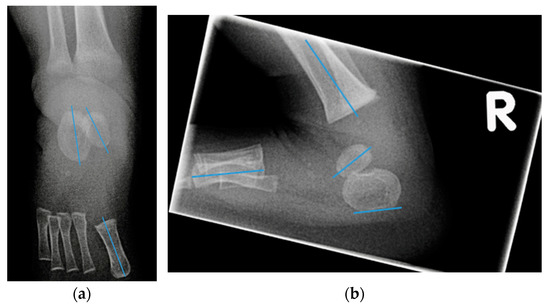

On an AP radiograph (Figure 1a):

• Talocalcaneal angle (AP talocalcaneal): the angle between the long axes of the talus and calcaneus. This measurement describes the eversion of the calcaneus under the talus. A small value indicates hindfoot varus [9].

• Talo first metatarsal angle (AP talo 1st MT): the angle between the long axis of the talus and 1st metatarsal. This measurement describes forefoot abduction or adduction [9].

On a lateral radiograph with maximum dorsiflexion (Figure 1b):

• Lateral tibial calcaneal angle (lat tibiocalcaneal): the angle between longitudinal axis of the tibia and the plantar aspect of the calcaneus. This measurement describes equinus deformity.

• Lateral talo calcaneal angle (lat talocalcaneal): the angle between the long axis of the talus and the plantar aspect of the calcaneus. Parallel lines indicate inversion between talus and calcaneus, thus hindfoot varus [9,16,17].

• Lateral talo first metatarsal angle (lat talo 1st MT): the angle between the long axis of the talus and the first metatarsal. This measurement describes the presence of cavus deformity.

• Lateral calcaneal 1st metatarsal angle (lat calcaneal 1st MT): the angle between the plantar aspect of the calcaneus and the long axis of the first metatarsal. This measurement also describes the presence of cavus deformity.

• Foot dorsiflexion between the tibia and a radiolucent wooden board in maximum dorsiflexion (lat foot dorsiflexion). This measurement describes equinus.

Figure 1. Radiograph obtained at the age of three months: (a) anteroposterior radiograph with lines through the longitudinal axis of the talus, calcaneus, and 1st metatarsal; (b) lateral radiograph with lines through longitudinal axis of the tibia, the talus, the 1st metatarsal, and the plantar aspect of the calcaneus.